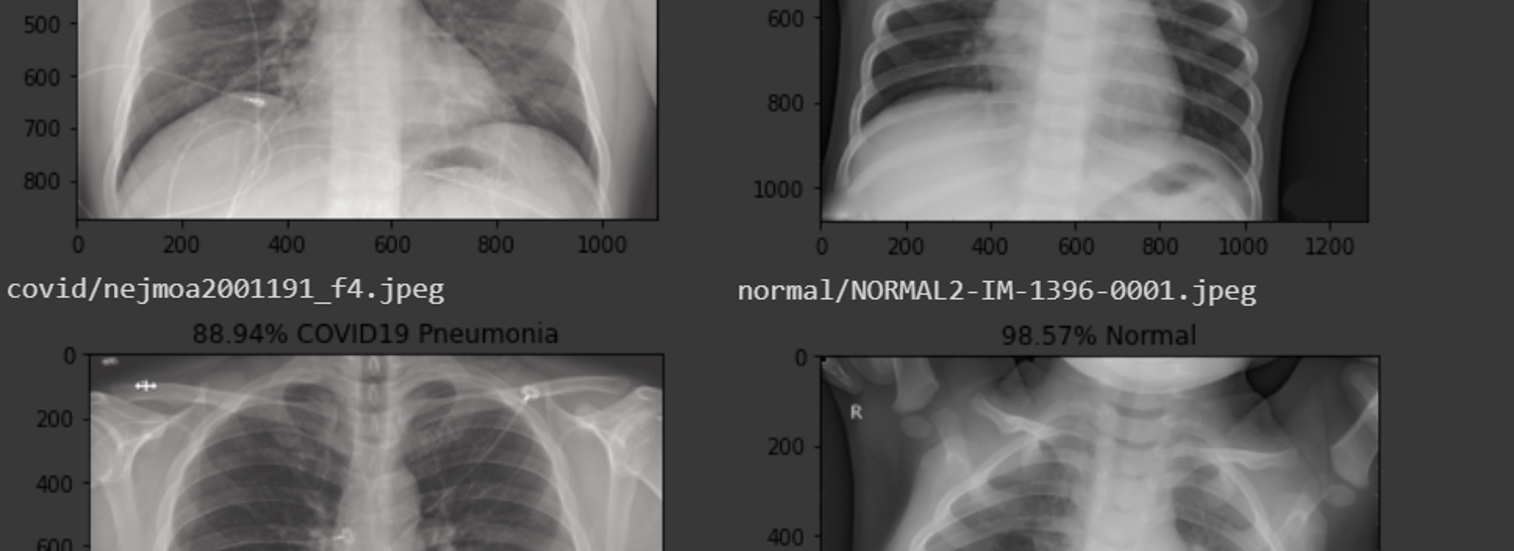

Detecting Covid 19 In X Ray Images With Keras Tensorflow And Deep Learning Pyimagesearch